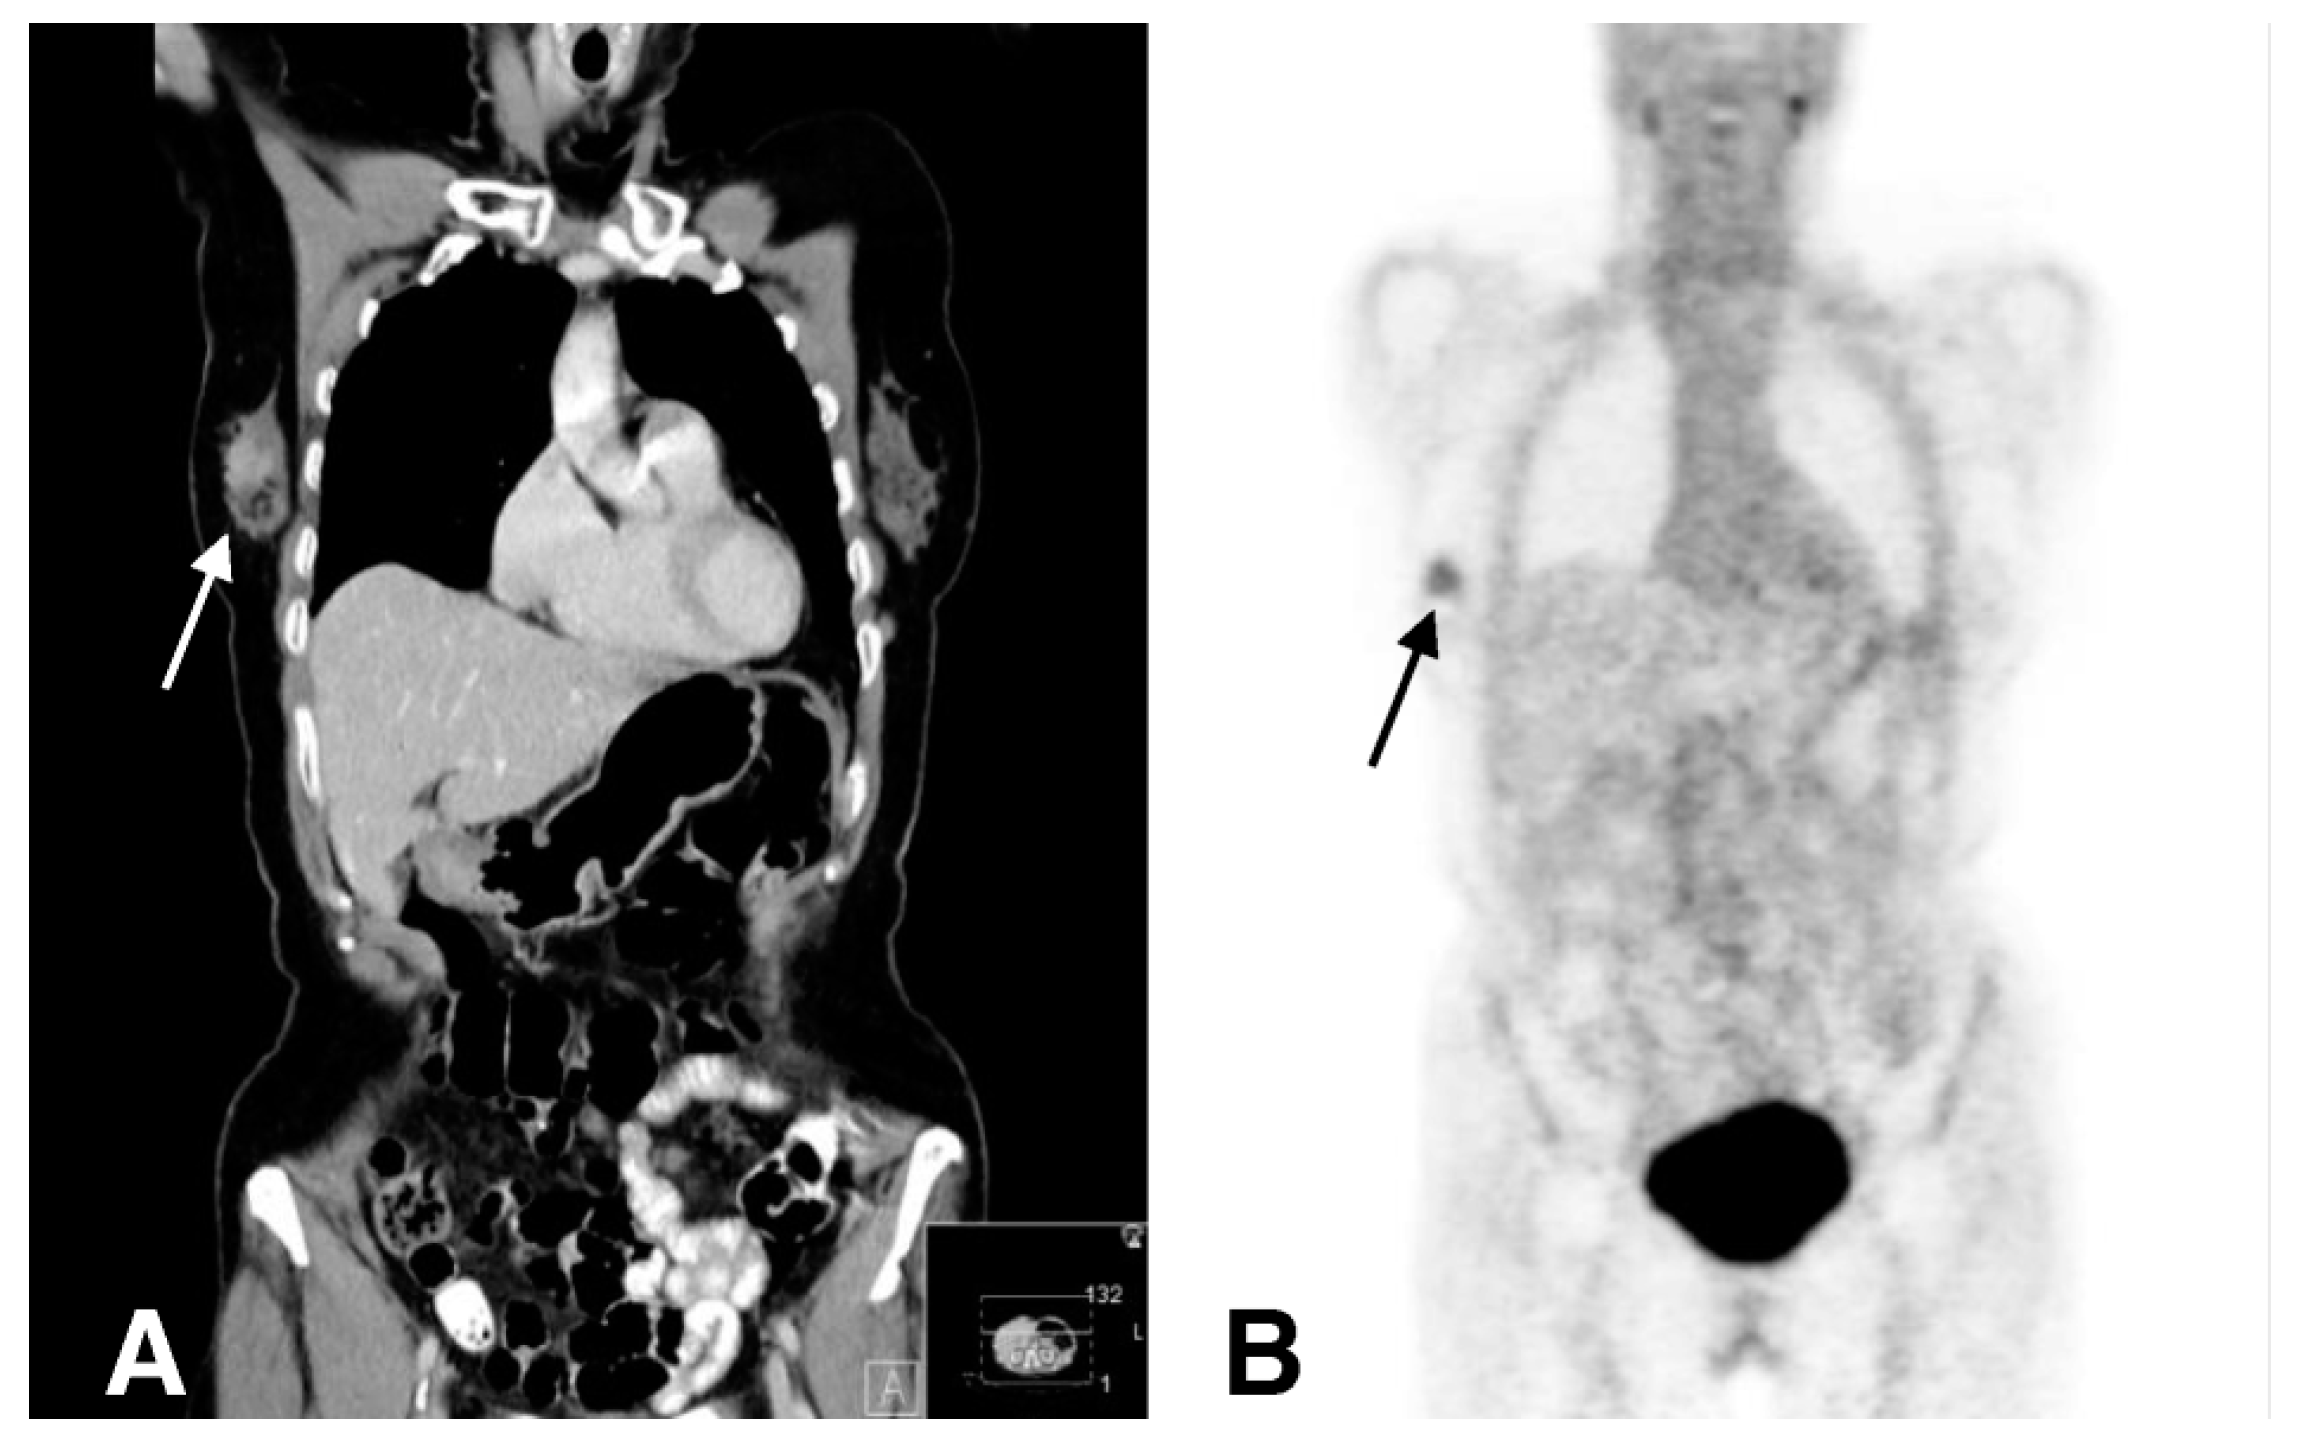

- Vag, T.; Gerngross, C.; Herhaus, P.; Eiber, M.; Philipp-Abbrederis, K.; Graner, F.P.; Ettl, J.; Keller, U.; Wester, H.J.; Schwaiger, M. First Experience with Chemokine Receptor CXCR4-Targeted PET Imaging of Patients with Solid Cancers. J. Nucl. Med. 2016, 57, 741–746. [Google Scholar] [CrossRef]

- Vag, T.; Steiger, K.; Rossmann, A.; Keller, U.; Noske, A.; Herhaus, P.; Ettl, J.; Niemeyer, M.; Wester, H.J.; Schwaiger, M. PET imaging of chemokine receptor CXCR4 in patients with primary and recurrent breast carcinoma. EJNMMI Res. 2018, 8, 90. [Google Scholar] [CrossRef] [PubMed]